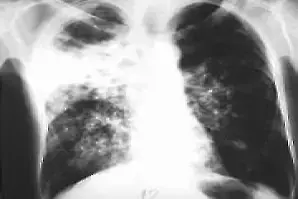

Въпреки великото откритие и до днес проблемът съществува. Всяка секунда някой по света се заразява от туберкулоза. На всеки 20 секунди някой по света умира от туберкулоза. Ако пациент с активна белодробна туберкулоза не се лекува, може да зарази 10-15 души годишно. Появи се и нов сериозен проблем - пациенти с мултирезистентна форма на туберкулоза, вследствие на неправилен лечебен режим, неспазване и прекъсване на лечението. Тези пациенти не могат да се лекуват с обичайните лекарствени средства. Преди 21 години СЗО обяви туберкулозата за глобална заплаха за човечеството. В много държави, както и в България бяха разработени и започнаха да действат Програми за ограничаване на заболеваемостта от туберкулоза чрез профилактика, ранна диагноза и лечение.

Първите резултати от изпълнението на тази програма са: снижаване на заболеваемостта в страната - от 39 на 100 000 души за 2006 год. на 30 на 100 000 души за 2010 г.